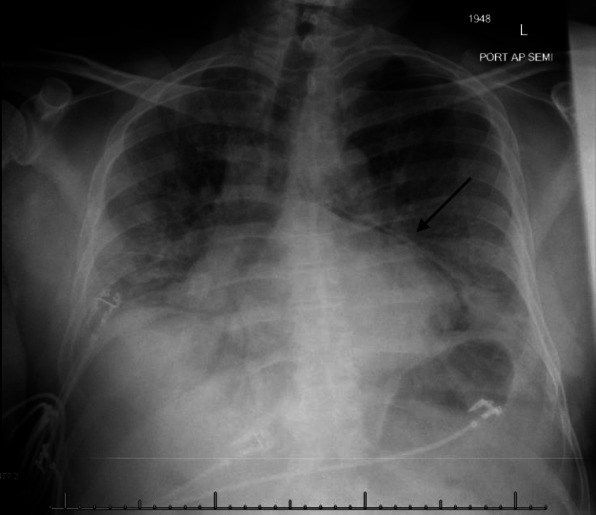

Fig. 3.

A frontal chest radiograph of Patient 2 showing interval development of spontaneous pneumomediastinum and possible pneumopericardium (arrow)